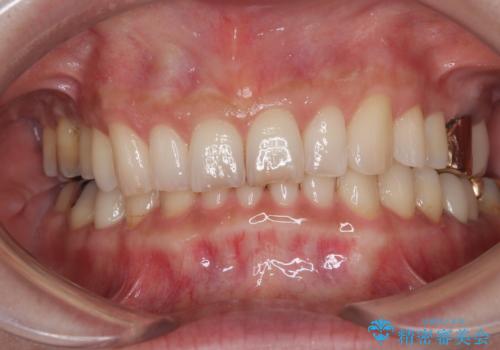

![[突き出た前歯を引っ込めたい] ワイヤー矯正とマウスピース矯正の併用治療の症例 治療後](https://seimitsushinbi.jp/wp/wp-content/uploads/2024/08/IMG_9725-500x350.jpg?v=1723179307)